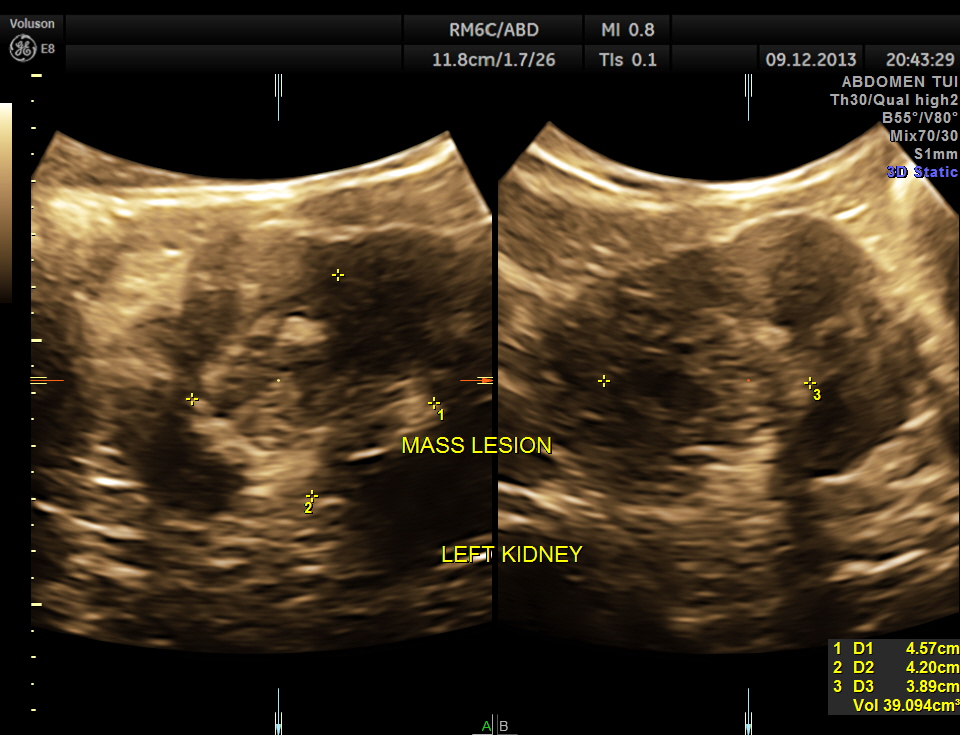

The pictures of the left kidney are given below. An echogenic mass lesion is seen .

3D View of the mass.

The findings were confirmed with CT Scan . he underwent radical left nephrectomy and the biopsy was reported as RENAL CELL CARCINOMA.

The images presented above show certain features better seen with reconstruction . But the diagnosis as is usual is made out with the 2 D images .